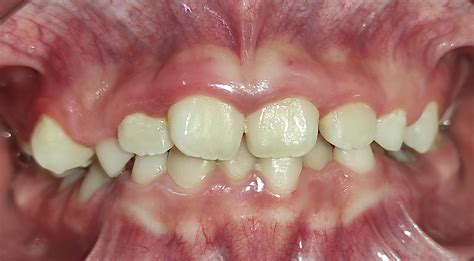

La hipoplasia maxilar es una condición que se caracteriza por un subdesarrollo del hueso maxilar superior, lo que puede causar problemas tanto de alineación dental como de apariencia facial. Este problema no solo afecta la estética facial, sino que también puede tener un impacto funcional en la vida diaria. Las personas con esta afección suelen presentar:

- Una mandíbula que sobresale en comparación con la parte superior del rostro.

- Mordida cruzada o problemas de alineación dental.

- Mordida cruzada o abierta: La alineación de los dientes no es correcta.